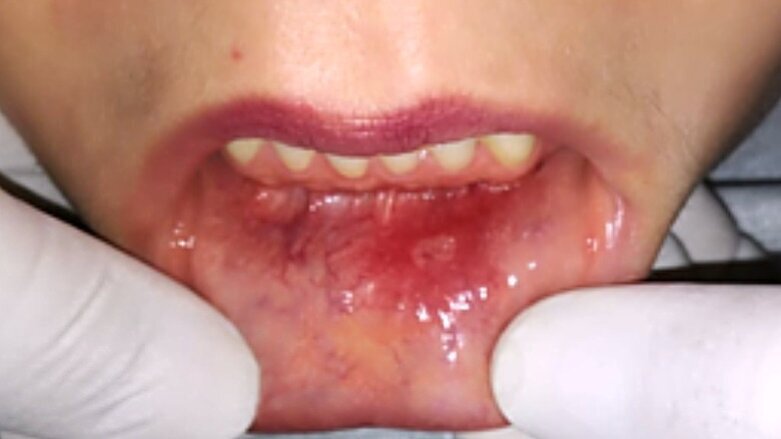

Al examen intraoral, se evidencia lesión a nivel de la mucosa vestibular cercana a línea media y labio inferior con aspecto eritematoso, pérdida de epitelio y sintomatología dolorosa, de diámetro aproximado de 20 mm; clínicamente es compatible con afta bucal (Figura 1).

Figura 1. Lesión a nivel de la mucosa vestibular con aspecto eritematoso, pérdida de epitelio y sintomatología dolorosa, compatible con afta bucal.